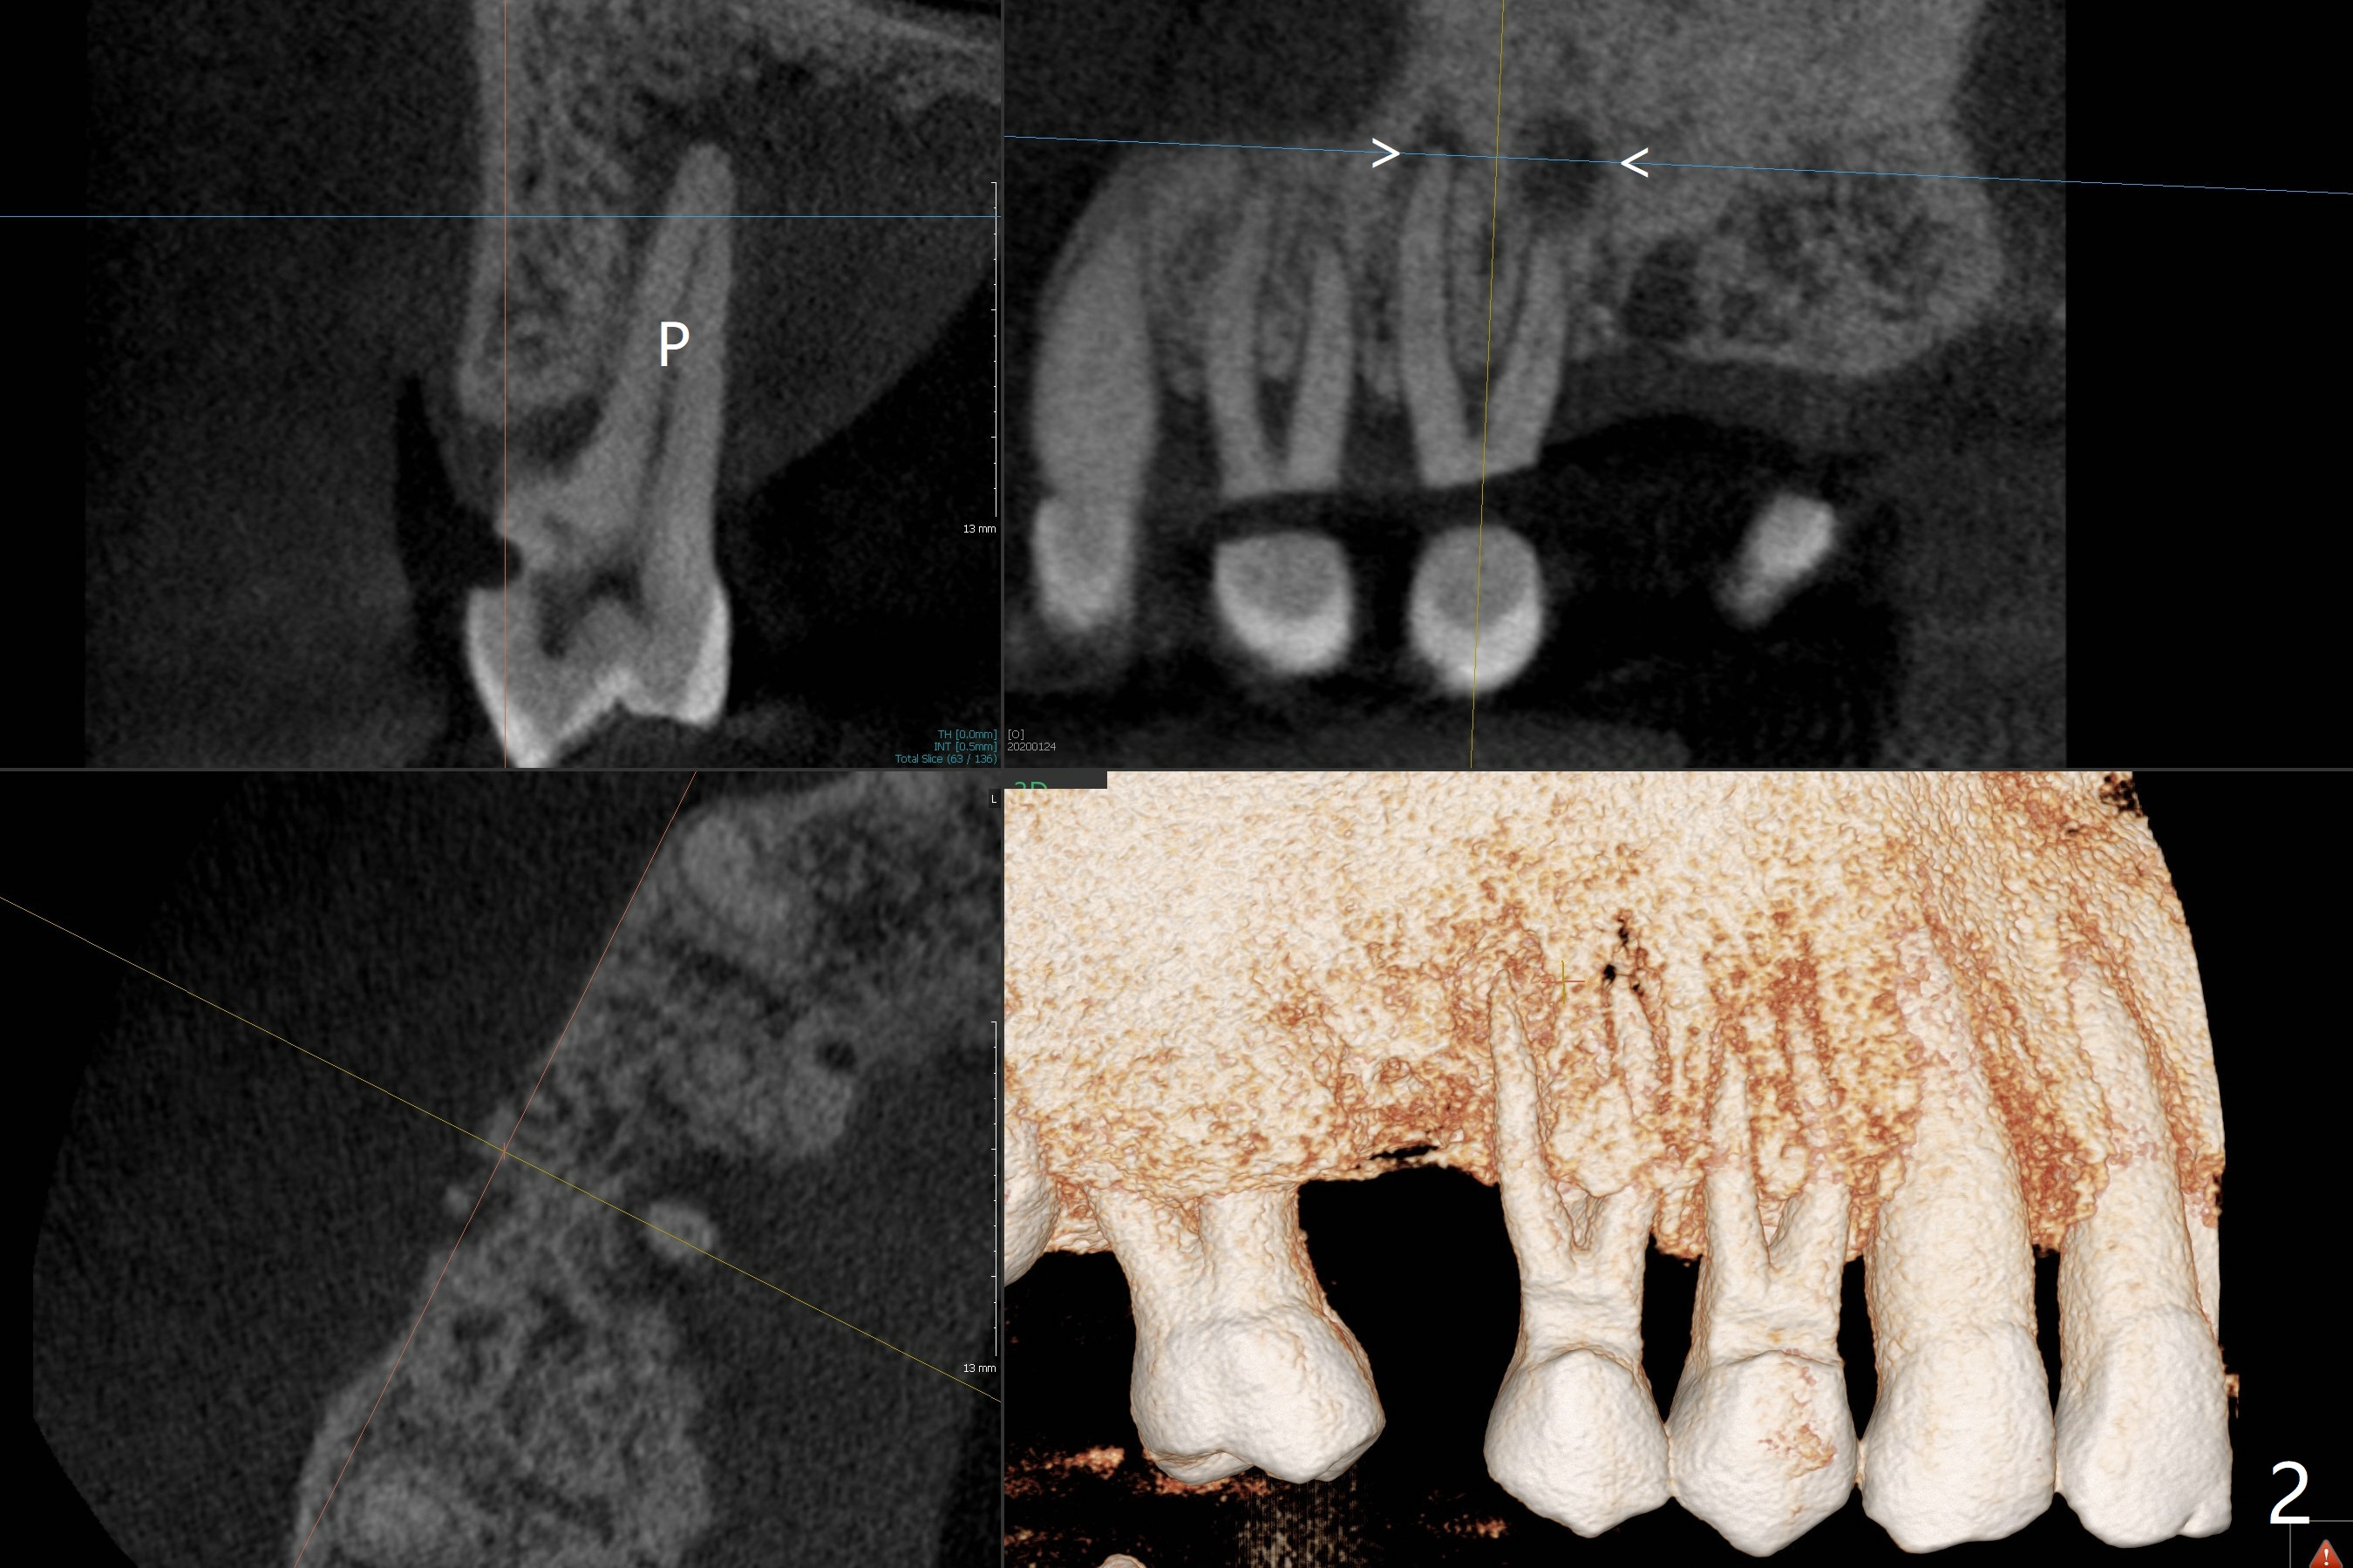

A 52-year-old man (smoker 1 ppd) has toothache in UR. The tooth #4 has severe Class V defect (Fig.1 *), periapical radio-lucency (PARL, arrow-heads) around the buccal roots and mild percu-ssion. PARL is more severe around the palatal root (Fig.2 P). Since it seems difficult to do socket preser-vation, can we do RCT to regrow bone before implant? CT coronal section shows the palatal defect of the palatal root (Fig.3,4), while sagittal one shows J defect of the palatal root, associated with root fracture (Fig.5). In fact the palatal root has transverse fracture at crestal level (Fig.6-8). The tooth #4 will be extracted for immediate implant (Fig.9,10); a 4 mm implant will be placed in the narrow space of #3 at the same time (Fig.11). The patient had symptoms consistent with aortic aneurysm. Since then smoke has been quit.